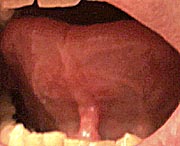

Depending on the reference, between two and five percent of all babies are born with some degree of tongue tie (ankyloglossia) where the thin sheet of flesh (lingual frenum, or frenulum) that connects the underside of the tongue to bottom of the mouth prevents the tongue from protruding from the mouth.

Adult

lingual frenum

This can be caused by the frenum being too short or extending too far toward the tip of the tongue. In serious cases babies may not be able to suckle properly and if left uncorrected will lead to speech problems. Minor cases can be left uncorrected and the individual will live a completely normal and fully functional life. Many people have some degree of tongue tie and never know it. As long as the degree of tongue tie in a child is small enough that it doesn't interfere with feeding or speech many doctors prefer to leave it alone. Sometimes the severity of the condition diminishes as the individual matures.

My lingual freedom increased the length I could stick my tongue out from 16mm to 28mm, or 1/2-inch. This may not sound like much of an improvement but it has to be remembered that the frenum isn't the only thing that determines how far out a tongue can be extended. The length of the tongue itself is the most important factor. Visually there isn't much difference. A close look at the frenum now shows that the thick band of white tissue on the leading edge of the frenum is now gone.